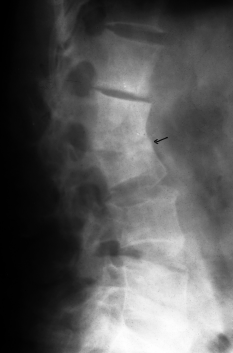

病例3,女,39岁,腰椎破坏3年,食用7个月痊愈。治疗前第2、3腰椎骨质破坏(a),有窦道流脓水。治疗后坏死灶消失,窦道愈合,骨质硬化(b).

Case 3. Repair of bone tuberculosis: female, 39 years old, 3 years old, cured with antituberculosis drugs for 7 months. Bone destruction of the 2nd and 3rd lumbar vertebrae before eating (a). The necrosis of the 2nd and 3rd lumbar vertebrae disappeared and osteosclerosis (b).